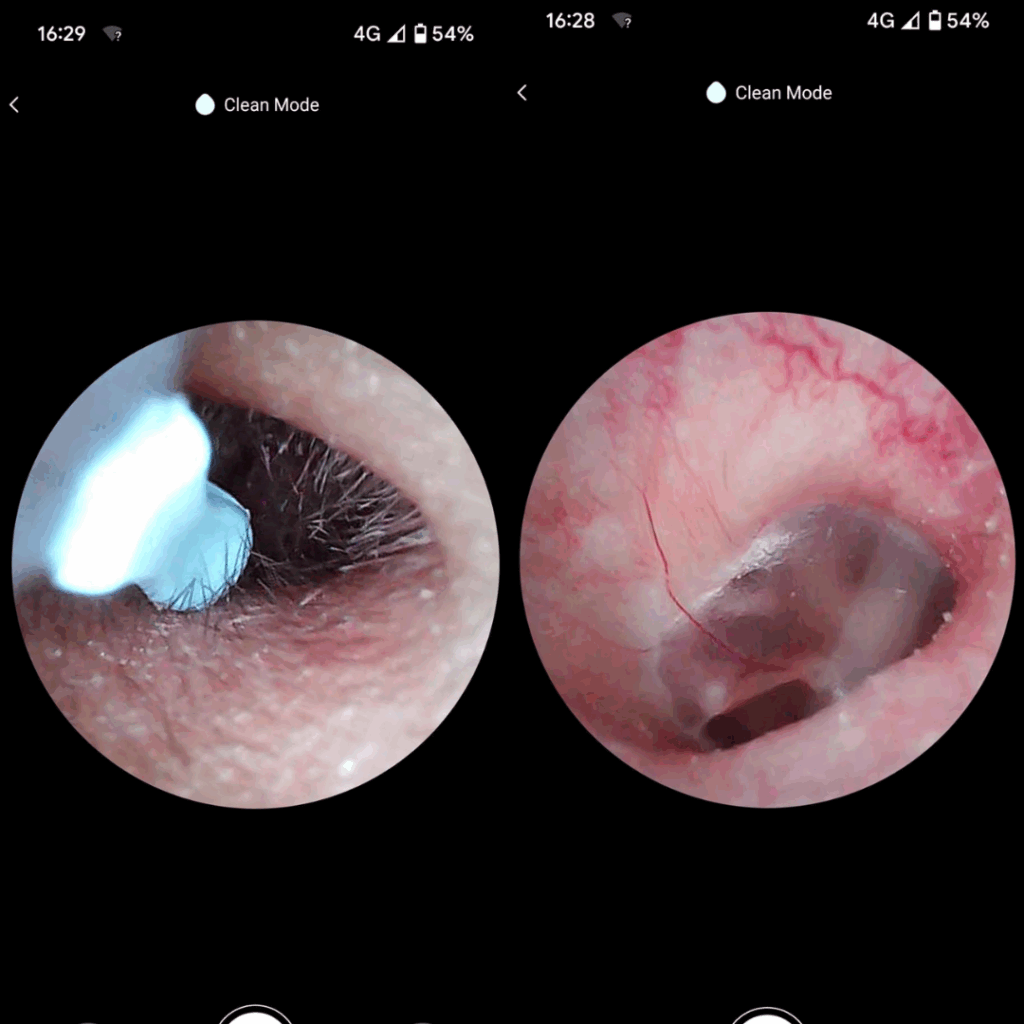

✅ Wyraźny obraz HD – dokładna widoczność wnętrza ucha dzięki kamerze 1080p

Koniec z ryzykiem urazów i infekcji — patyczki często powodują podrażnienia, infekcje i perforację błony bębenkowej. Pełna kontrola dzięki obrazowi HD 1080p — widzisz woskowinę i swobodnie ją usuwasz, zamiast ją wpychać.

Pełna kontrola dzięki obrazowi HD 1080p — widzisz woskowinę i swobodnie ją usuwasz, zamiast ją wpychać. Miękkie silikonowe końcówki zamiast patyczków — precyzyjnie usuwa woskowinę, bez ryzyka zarysowań i dyskomfortu